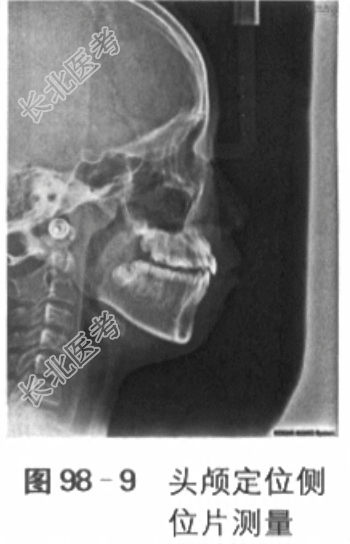

深,下中线左偏2mm,上牙弓狭窄,上前牙直立,重度拥挤,15腭侧错位,14、24颊侧错位,下颌3~3重度拥挤,22过小牙,口腔卫生良好,牙周健康。下颌可后退至切对切(见图98-1)。5.影像学检查6.模型分析(1)上牙弓拥挤度:未测量(13、23阻萌,15腭侧错位,重度拥挤)。(2)下牙弓拥挤度:4mm。(3)下颌Spee曲度:4mm。(4)前牙Bolton比:80.3%。(5)全牙Bolton比:92.7%。二、诊断与诊断依据(1)骨性Ⅲ类,上颌轻度发育不足,下颌轻度发育过度:头颅定位侧位片测量值显示SNA78°,SNB80°,ANB-2°,Ao-Bo-8mm,APDI95°。(2)安氏Ⅲ类:前牙反

,第1恒磨牙近中关系。(3)牙列拥挤:全景片显示上颌双侧尖牙阻萌,模型测量显示下颌拥挤度为4mm,上颌15腭侧错位。(4)13、23阻生可能。